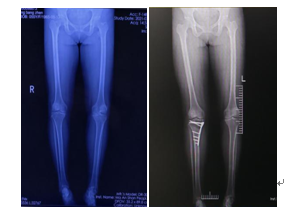

病例1:55歲的女性李某,在關(guān)節(jié)骨科行“脛骨高位截骨術(shù)”治療膝關(guān)節(jié)骨關(guān)節(jié)炎,術(shù)后患者非常滿意。

病例2:71歲的男性張某,行“膝關(guān)節(jié)單間室置換術(shù)”治療膝骨關(guān)節(jié)炎,術(shù)后患者非常滿意。